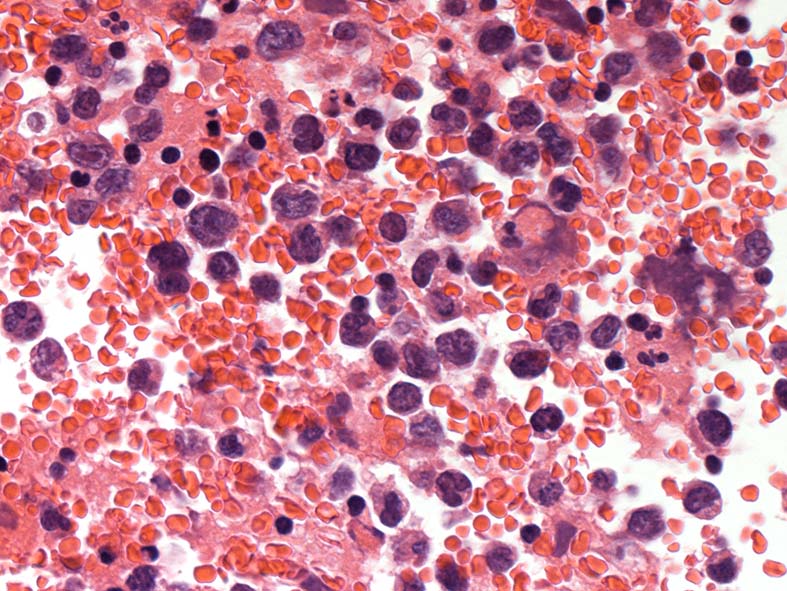

心タンポナーデの診断で心嚢液穿刺ドレナージ. 心嚢液内に多数の異型細胞増加が認められた.心嚢液smear標本. Giemsa染色

小型リンパ球の3-4倍, 空胞の多い青色調の細胞質をもった大型異型細胞が増殖. 核クロマチンは微細顆粒状, 繊細で核小体が1-数個認められる. 二核の異型細胞がある.

ALL-L3やBurkittリンパ腫細胞に類似した腫瘍細胞で, 疾患説明のplasmablastsやALKの細胞とは形態が異なって見える.